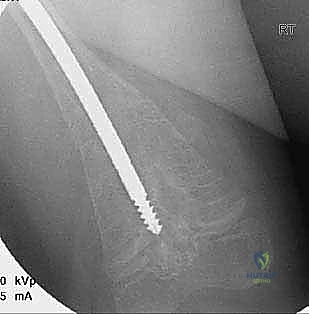

قبل العملية، يقوم الدكتور هطيف بإجراء دراسة شاملة لصور الأشعة السينية (X-rays) المأخوذة بدقة، لحساب زوايا التقوس بدقة متناهية، وتحديد نقاط بضع العظم (أماكن القص)، واختيار الحجم والطول المناسبين للمسمار التلسكوبي.

الخطوة الرابعة: إدخال المسمار التلسكوبي

بعد تقويم العظم وجعله مستقيماً كحبات المسبحة على خيط، يتم إدخال السلك الدليلي (Guide Wire). ثم يتم إدخال الجزء الخارجي (الأنثوي) من المسمار التلسكوبي وتثبيته في الجزء العلوي من العظم (Epiphysis).

بعد ذلك، يتم إدخال الجزء الداخلي (الذكري) من المسمار عبر الجزء السفلي من العظم وتثبيته في المشاشة السفلية. هذا التصميم العبقري يضمن حماية العظم بالكامل من الداخل.

كان عمار يعاني من النوع الثالث من تخلّق العظم الناقص، مع تقوس شديد في عظمي الفخذين (بشكل حرف O) منعه من المشي تماماً، وجعله حبيس الكرسي المتحرك، مع تاريخ من 8 كسور سابقة. تم إجراء عملية بضع العظم المتعدد عبر الجلد وتركيب مسامير فاسييه-دوفال التلسكوبية في كلتا الساقين في جلسة جراحية واحدة بواسطة الدكتور هطيف. اليوم، وبعد 6 أشهر من الجراحة، يمشي عمار مستقلاً لأول مرة في حياته، ولم يتعرض لأي كسر جديد.

عانت رؤى من كسور متكررة في عظم القصبة (الساق) بمجرد محاولتها الجري. أظهرت الأشعة هشاشة شديدة وتقوساً أمامياً. بعد استشارة الأستاذ الدكتور محمد هطيف، تقرر إجراء التدخل الجراحي المحدود. تم تصحيح التقوس بنجاح باهر، وبفضل المسمار التلسكوبي الذي ينمو معها، عادت رؤى للعب مع أقرانها بثقة وأمان.